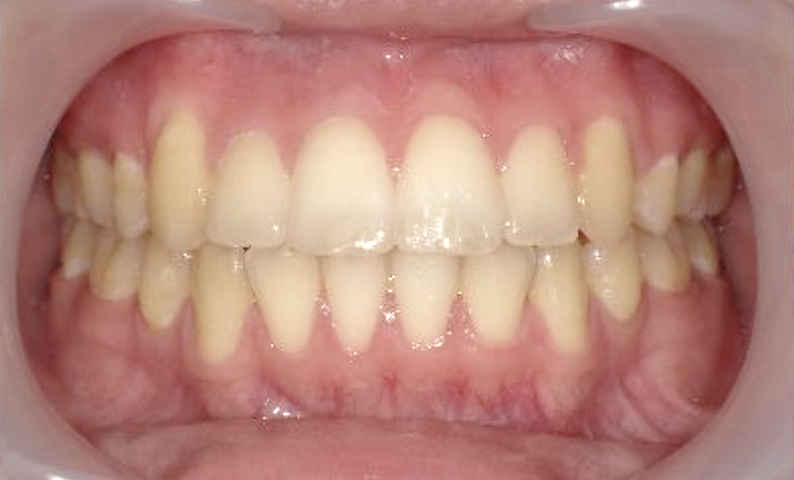

症例_004 上下顎の部分矯正

治療期間:8ヶ月金額:54万円+税女性前歯のガタガタ捻転歯

| Before | After |